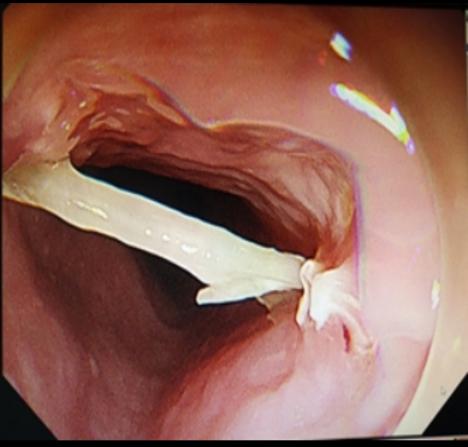

第二步:立即就醫(yī)內(nèi)鏡中心是首選??捎秒娮游哥R直觀地發(fā)現(xiàn)并取出食道的異物。

團(tuán)塊異物: 大塊的肉、果核、糯米團(tuán)等

危害: 這是最危險(xiǎn)的做法!尖銳的異物(如魚刺)可能在強(qiáng)行吞咽過程中被推得更深,甚至刺穿食道壁。一旦傷及緊貼食道的主動(dòng)脈,可能引發(fā)致命性大出血。